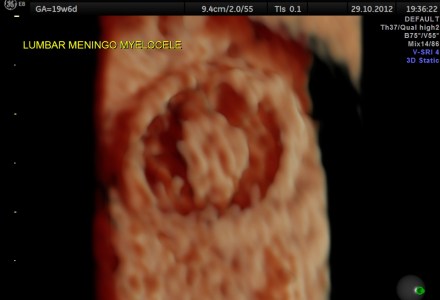

SPINA BIFIDA -OPEN NEURAL TUBE DEFECT 3D IMAGES

NEURAL TUBE DEFECT